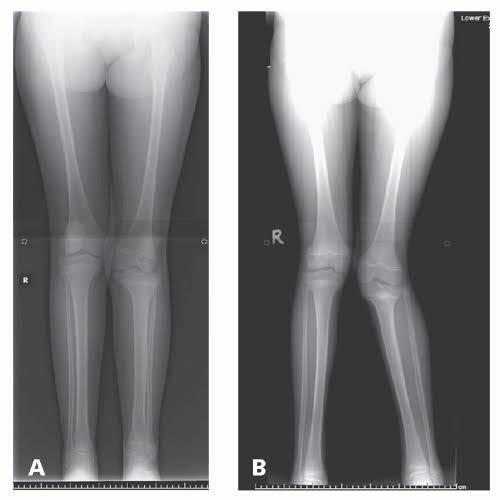

What is Genu Valgum (X-legs)?

Genu valgum, commonly known as knock knees or X-legs, is a condition where the knees angle inward and touch each other while the ankles remain apart when standing with the feet together. This inward angulation results in a gap between the feet, giving the appearance of inward-bending legs. Genu valgum definition highlights it as a condition often seen in young children as part of their normal growth and development, but it can also persist into adulthood if not properly addressed. The genu valgum meaning encompasses both its occurrence in childhood and potential persistence into adulthood. Can genu valgum be corrected? Yes, it can.